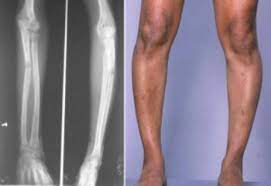

Raşitizmli bazı çocukların göğüs kafesleri düzleşip göğüs kemiklerinin ileri çıkmasına neden olabilecek anormallikler gelişir. Her ne kadar Sağlıklı bebeklerin bacaklarında bile biraz çarpıklık olsa da, raşitizmde bacakların abartılı şekilde eğilmesi olarak gözlemlenir.

Doktor eğer raşitizmden şüphelenirse, etkilenen kemiklerin röntgeninin çekilmesini isteyebilir. Bu röntgen filmi kemik deformitelerini ortaya çıkarabilir. Buna ek olarak yapılacak kan ve idrar testleri, hem raşitizm teşhisini doğrulayabilir ve hem de sebebinin belirlenmesine yardımcı olarak nasıl bir tedavinin kullanılması gerektiğini belirleyebilir.